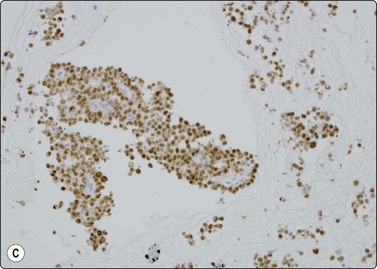

image image image

Fig. 11.7 Solid-pseudopapillary neoplasm

(A) Vessel associated pseudopapillary fragment (Pap, LP); (B) Pseudopapillary fragment. Note small tumor cells and irregular outer border with detached tumor cells (MGG, IP); (C) Cell block section showing positive staining for progesterone receptors (PR, IP).

Solid-psedopapillary neoplasm (Figs 11.7 and 11.8)

Criteria for diagnosis

Extremely cellular,

Branching papillary fronds comprising central slender fibrovascular cores of myxoid stroma lined by one or more layers of neoplastic cell which are exfoliating with dispersal,

Acinar arrangements with central metachromatic material (pseudorosettes),

Small epithelioid cells with bland round to oval nuclei, occasional longitudinal nuclear grooves, finely granular chromatin and inconspicuous nucleoli,

Balls or globules of PAS-positive myxoid stroma and psammoma bodies,

Background of foamy macrophages, multinucleated cells and necrosis.

This relatively uncommon low malignant potential pancreatic neoplasm, with its many pseudonyms, occurs almost exclusively in young women under the age of 20 years.64 They usually behave in a benign manner but 10–15% of cases show spread or metastases. Still considered to be of uncertain histogenesis, this tumor is thought to be hormonally dependent. Occurring anywhere along the length of the pancreas, the mass is usually sizeable at presentation, averaging 8 cm. Grossly, as well as on imaging studies, it is characterized by good circumscription, multiloculation and solid and cystic areas. The histopathologic features, which are specific and diagnostic, are mirrored exactly by the cytologic pattern in FNB smears. Initial tumor growth is solid, but degeneration results in clefts, eventually enlarging to cysts, between vascularized cell fragments, which then appear ‘pseudopapillary’.

Fifty isolated case reports or limited series attesting to the ability of FNB to confidently identify this unusual but widely reported neoplasm were summarized in 2002 by Pettinato and colleagues in a definitive paper.64 Richly cellular smears demonstrate characteristic pseudopapillae and pseudorosettes, composed of small tumor cells adherent to delicate metachromatic fibrovascular stalks. Recognition of this stromal component is essential in distinguishing this tumor of relatively good prognosis from similar small-celled pancreatic neoplasms. The outline of both the pseudopapillae and the pseudorosettes appears irregular, due to exuberant exfoliation of single cells into the smear background. These vascular-based aggregates vary from large grape-like branching structures to single capillaries with leaf-like single-cell linings (Fig. 11.7). These cells are small, round to oval, plasmacytoid or cuboidal and extremely monotonous. Cytoplasm is variably preserved, vesicular to faintly granular, containing characteristic eosinophilic, hyaline intracytoplasmic globules, which are PAS positive. Nuclei are round and even, with grooves but no major irregularities or significant pleomorphism. Chromatin is described as finely granular, without clumping or clearing. Small nucleoli may be appreciated and are occasionally multiple. In the background, foam cells, multinucleated giant cells, debris and laminated psammoma bodies reflect the cystic and papillary nature of the parent tumor. Mucus is absent. Diagnostic accuracy of EUS-FNA has been reported as 75% in a series of 28 cases.65

Page 303

Immunocytochemistry is extremely variable but most neoplasms studied stain positively for vimentin, α1-antitrypsin, α1-antichymotrypsin and progesterone receptor (Fig. 11.7C). Unlike PET, they are typically negative for chromogranin, cytokeratin, EMA and specific pancreatic hormones. Both tumors may express CD10, synaptophysin and CD56.64,66-69 More recently, nuclear expression of beta-catenin together with loss of normal membrane localization of E-cadherin have been proposed as useful in separating the two entities.66,67,69